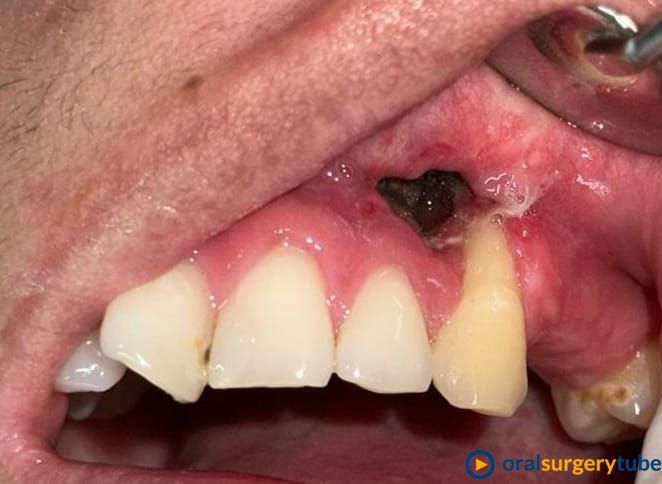

Buenas doctor, le escribo desde Chile, estudiante de la PUC a punto de egresar de su pregrado. En mi práctica clínica en Hospital, nos llega un caso de paciente de 21 años que se sometió a una cirugía de excisión de queratoquiste en maxilar superior, actualmente no ha presentado cicatrización en la zona del quiste lado izquierdo, el canino se encuentra con su raíz expuesta, la cavidad presenta fondo sucio, se ha realizado debridamiento, instalación de membrana con prf y sigue sin presentar mejoría. Me pregunto si usted recomendaría realizar un cierre con bola de bichat como opción, ya que los tratamientos realizados no han tenido resultados. Fui recomendada a sus casos por un Periodoncista del Hospital donde me encuentro, quien me encomendó realizar una revisión de posibles tratamientos para el caso. Agradecería su opinión, adjunto foto